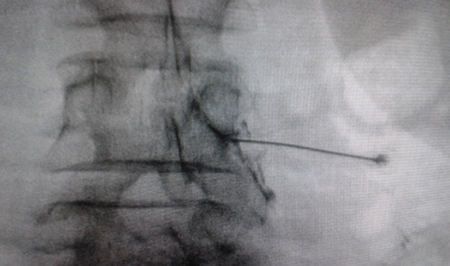

Figure 2